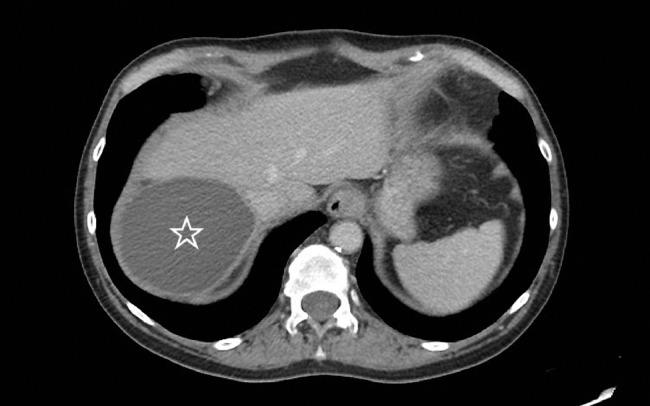

We describe the case of a 58-year-old female who presented to her primary care provider with lifelong anorexia, 6-week history of liquid only diet and new onset epigastric abdominal pain radiating to the back accompanied by nausea and abdominal distension. An initial computed tomography scan with contrast demonstrated a massive simple hepatic cyst with mass effect compression of the duodenal sweep. Repetitive treatment with aspiration sclerotherapy using hypertonic saline provided initial resolution of symptoms and led to substantial reduction of cyst diameter. Repeat imaging demonstrated complete drainage of the cyst and decompression of the duodenum. Ultimately, the patient's symptoms returned 6 weeks later at which time she opted for surgical deroofing of the cyst. Surgery provided for complete resolution. This case appears to be the first to document the compression of second portion of the duodenum by a massive simple hepatic cyst causing anorexia and mimicking gastric outlet obstruction.

我们描述了一名58岁女性的病例,她因长期厌食、仅接受流食6周的病史以及新发的上腹部疼痛并向后背部放射,伴有恶心和腹胀,就诊于她的初级保健医生处。最初的增强计算机断层扫描显示一个巨大的单纯性肝囊肿,对十二指肠曲有占位效应压迫。使用高渗盐水进行反复穿刺硬化治疗初步缓解了症状,并使囊肿直径大幅缩小。重复成像显示囊肿完全引流,十二指肠减压。最终,患者的症状在6周后复发,此时她选择了囊肿开窗手术。手术使症状完全缓解。该病例似乎是首例记录巨大单纯性肝囊肿压迫十二指肠第二段导致厌食并酷似胃出口梗阻的病例。